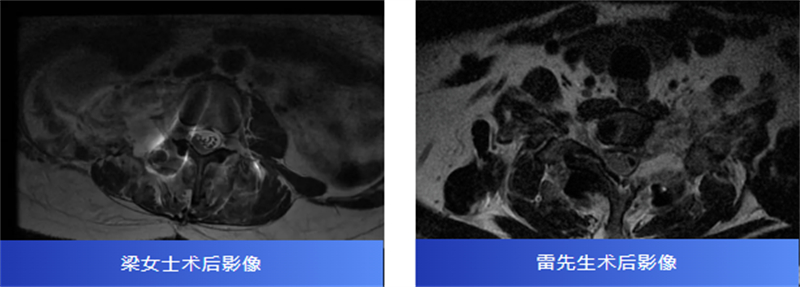

术中,在显微镜辅助下,医生精细分离肿瘤与神经组织,小心翼翼解除压迫,最终切除了肿瘤。病理报告也带来好消息:两人均为良性神经鞘瘤。

术后,梁女士的腰腿痛消失了,雷先生的颈肩胀痛也得到了缓解。两位患者都保住了正常的神经功能,步入康复的新阶段。